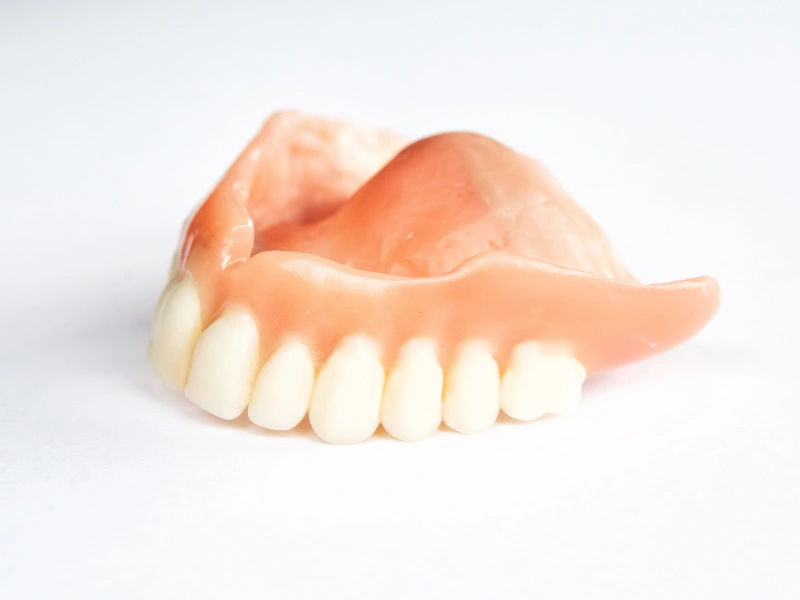

Atención integral en salud oral para toda la familia: desde controles de rutina hasta tratamientos de rehabilitación, estética y ortodoncia, en un mismo lugar.

Odontología integral Diagnóstico digital y preciso Enfoque preventivo y estético

Cuidamos tu salud oral en cada etapa

Especialidades dentales